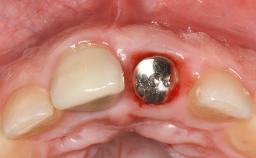

Peri-Implantitis Modified by the Presence of Submucosal Excess Cement: Reconstructive Therapy and a Ten-Year Follow-up

This case outlines the reconstructive therapy by Giovanni Salvi resulting in defect fill and inflammation-free peri-implant soft tissues at 10-year follow up. This case highlights the importance of regular monitoring of implants during supportive therapy.

A 30-year-old female patient was referred to the Department of Periodontology of the University of Bern, Switzerland, by a private dentist. Tooth 45 was congenitally missing and had been replaced with an implant three years prior to the first visit at the Department of Periodontology.